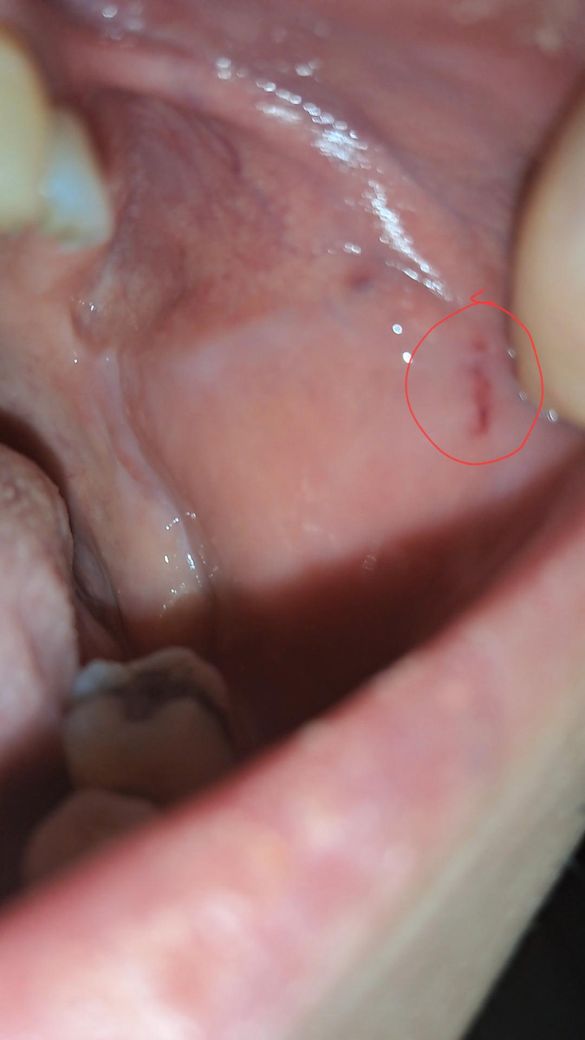

볼안쪽을 연속으로 두번 씹었는데 2주안에 안 나으면 병원가야 하나요

샌드위치 먹다가 연속으로 볼을 두번 씹었는데 거울로 확인해 보니 이렇게 됐어요

2주안에 안 나으면 큰병일 수 있다는데 병원 가봐야 하나요

상피세포 회복력이나 회복속도는 사람마다 약간 편차는 있습니다 단순 외상성 상처 같아서 크게 걱정은 안하셔도 될 것 같습니다

볼살이 씹혀서 상처가 생긴거 같습니다. 큰 문제가 잇는건 아니니 너무 걱정하지 않으셔도 됩니다 .